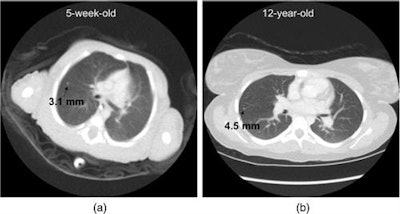

The researchers assessed radiation dose in terms of organ doses, effective dose, and risk index for 30 subjects in nine pediatric age-size groups. After also determining nodule detection accuracy, they used the results to set individual scan parameters for each patient group.

The resulting model can be used to optimize individual scan parameters and provide consistent diagnostic performance across the broad range of body sizes in children, the authors wrote.